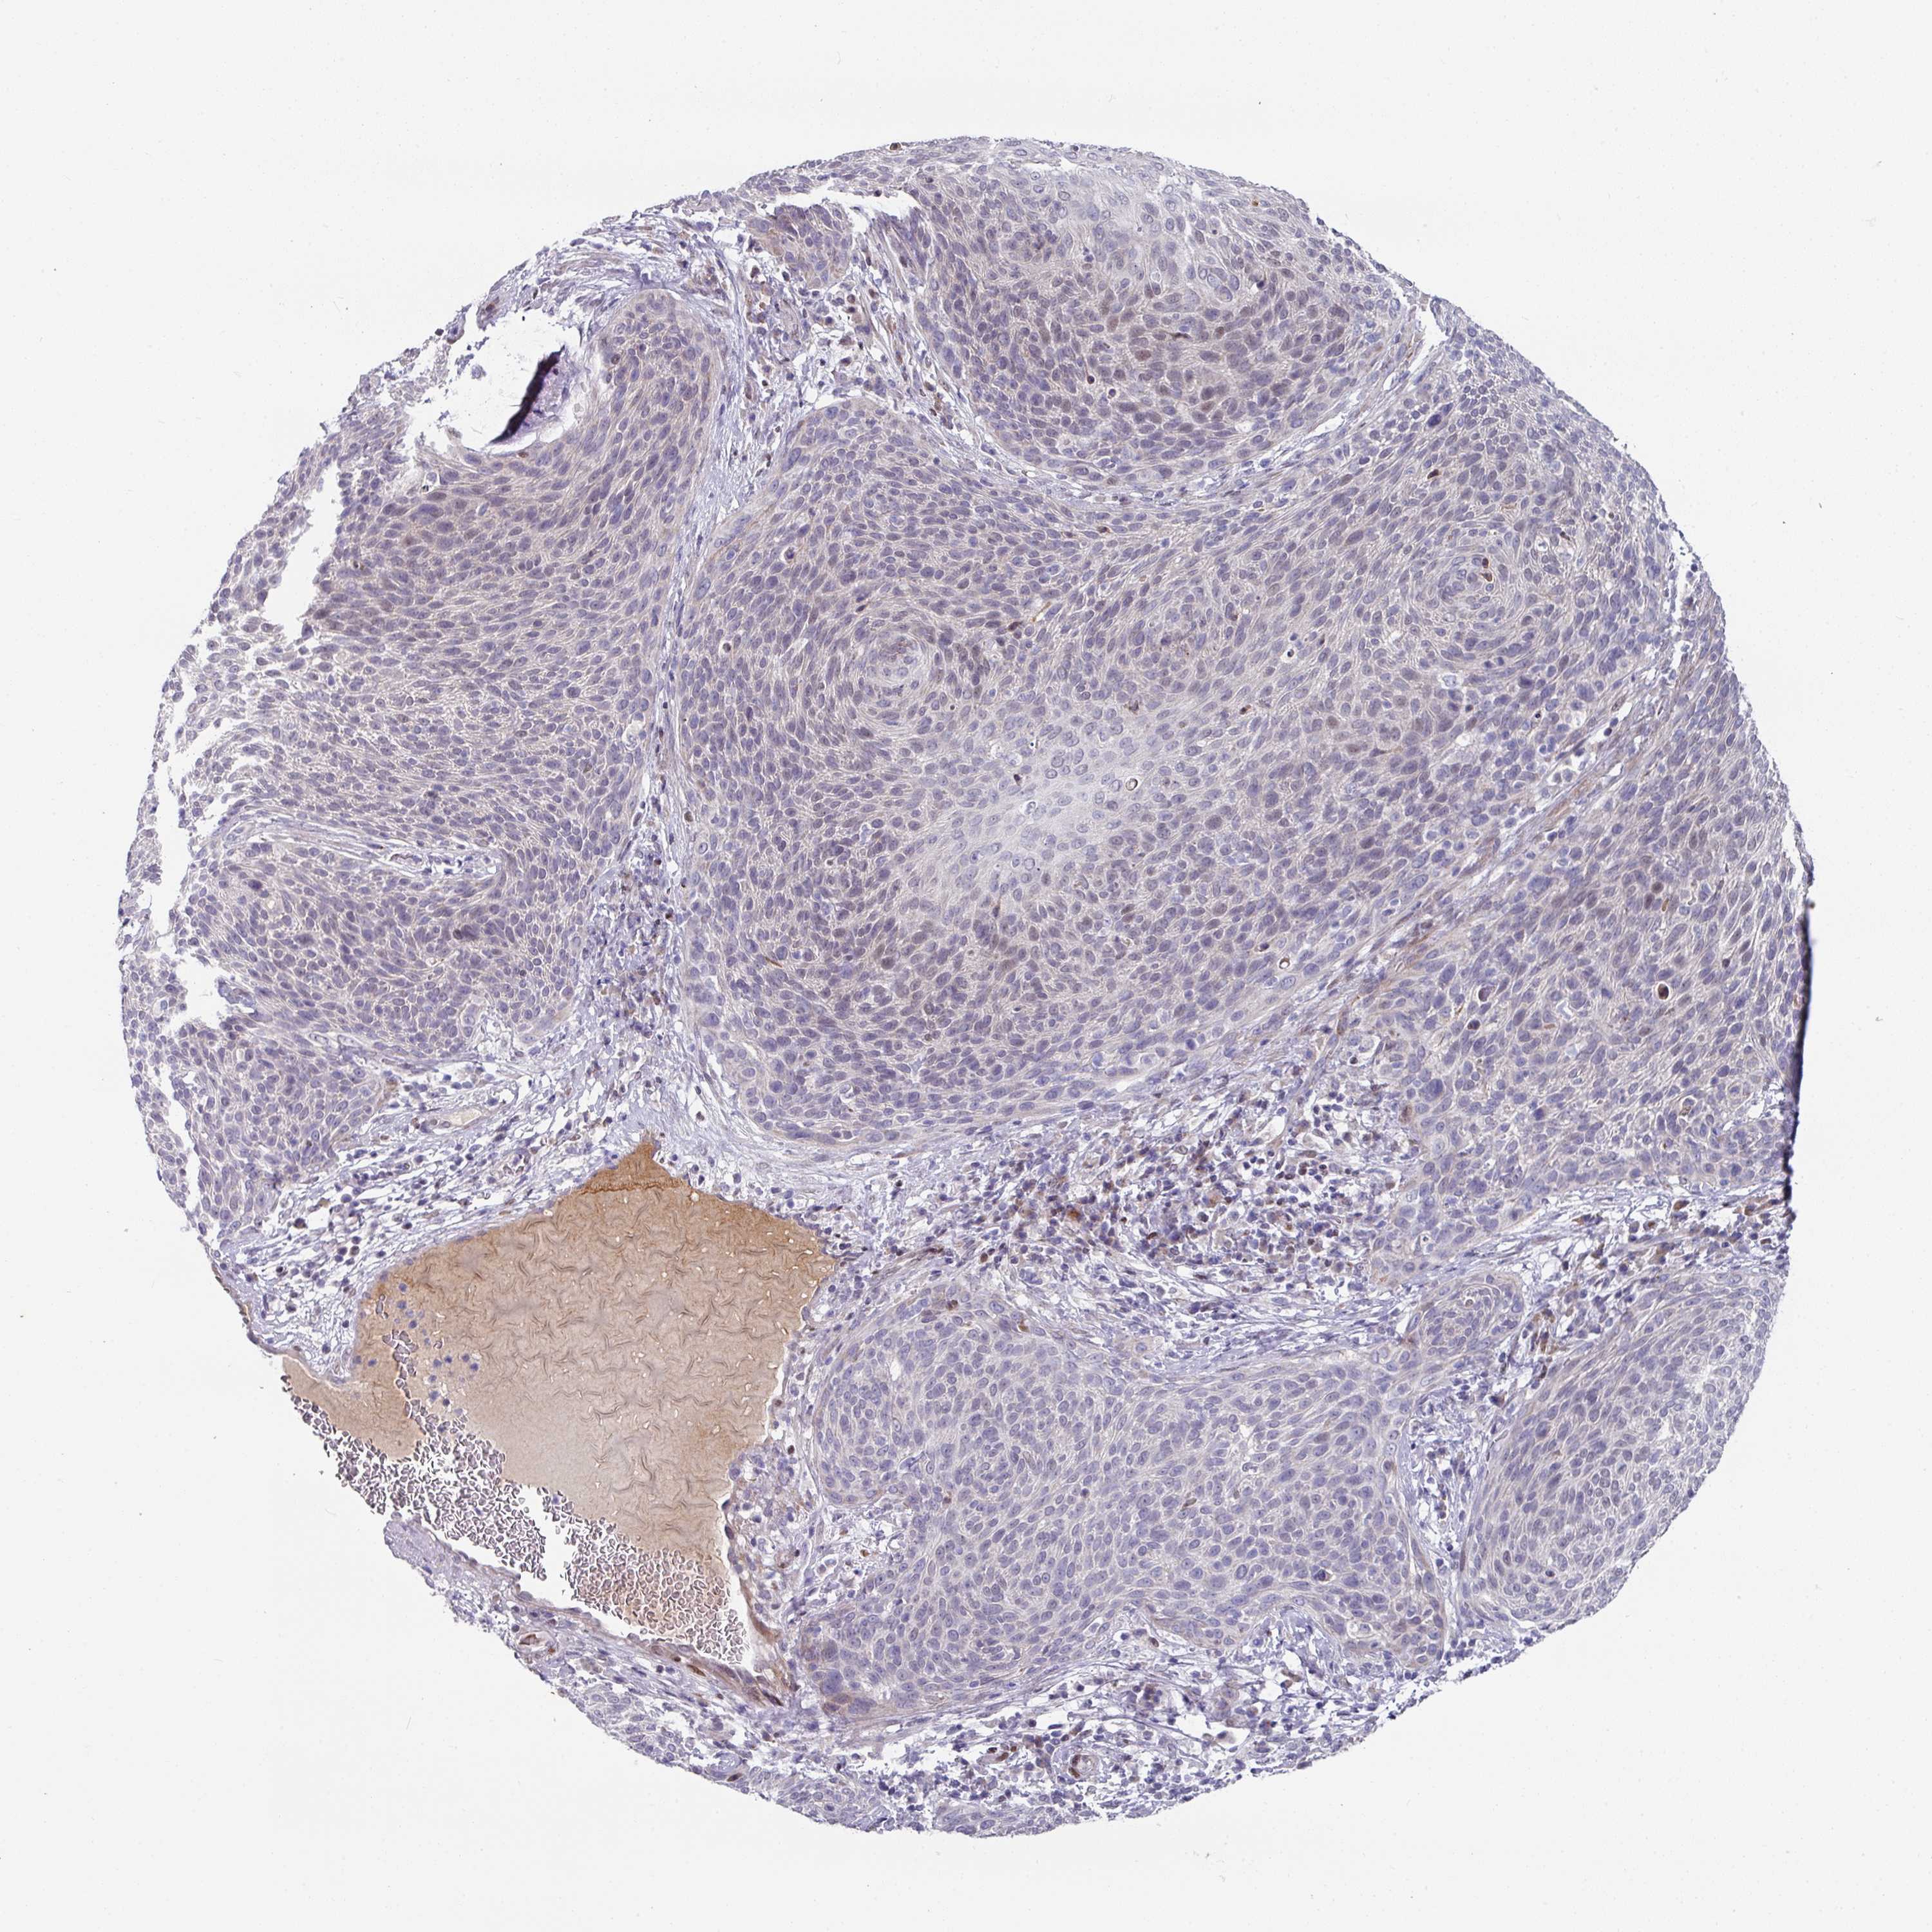

CERVICAL CANCER - Protein expressioni

A mouse-over function shows sample information and annotation data. Click on an image to view it in a full screen mode. Samples can be filtered based on level of antibody staining by selecting one or several of the following categories: high, medium, low and not detected. The assay and annotation is described here.

Note that samples used for immunohistochemistry by the Human Protein Atlas do not correspond to samples in the TCGA dataset.

Antibody stainingi

Antibody staining in the annotated cell types in the current human tissue is reported as not detected, low, medium, or high, based on conventional immunohistochemistry profiling in selected tissues. This score is based on the combination of the staining intensity and fraction of stained cells.

Each image is clickable and will lead to virtual microscopy that enables deeper exploration of all samples and also displays staining intensity scores, fraction scores and subcellular localization as well as patient and tissue information for each sample.

Antibody HPA048677

Antibody HPA056480

Antibody CAB011574

Staining

High

Medium

Low

Not detected

Intensity

Strong

Moderate

Weak

Negative

Quantity

>75%

75%-25%

<25%

None

Location

Nuclear

Cytoplasmic/membranous

Cytoplasmic/membranous,nuclear

Squamous cell carcinoma, NOS

Adenocarcinoma, NOS